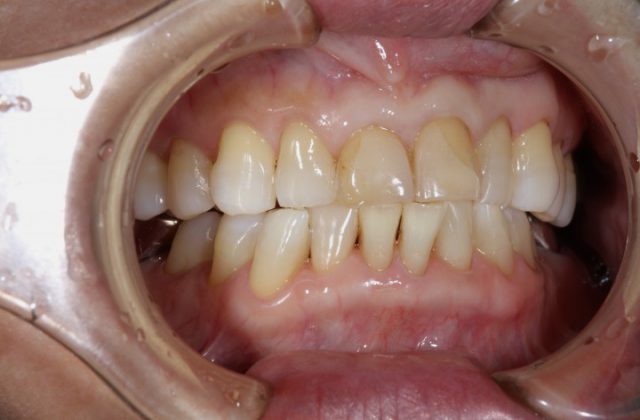

施術前

前歯の被せ物の取り替える場合はまわりの歯との色味をどこまで自然に合わせてくるかが重要になります。せっかく被せ物をやり直すからできるだけ白いものと思ってしまいそうですが、まわりの歯と色味が合わないと白くても違和感が出てきてしまいます。

術後の画像を見ていただいても分かりますようにまわりの歯と比べてもとても自然に仕上がります。おそらく近くでじっと見られても被せものであるとは分からないほど自然です。患者さまご本人も被せ物の仕上がりにとても喜んでおられました。